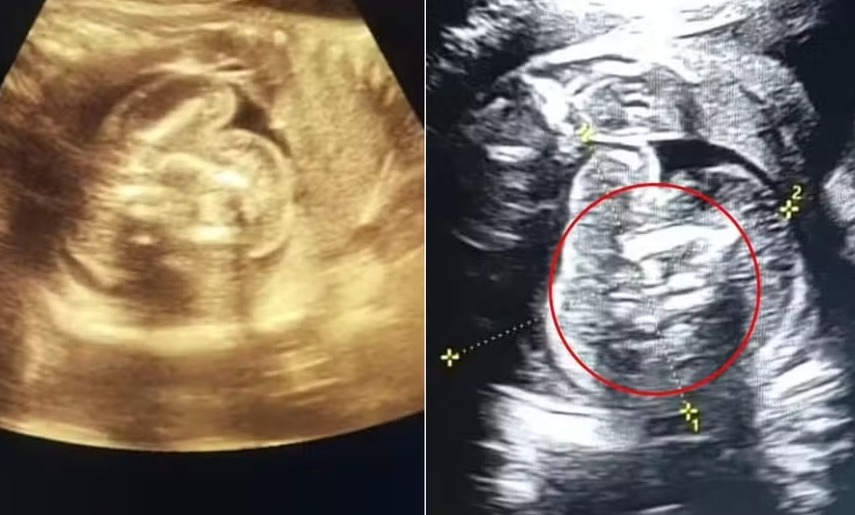

Uma mulher de 32 anos foi ao hospital na Índia para realizar um exame de rotina, aos 35 semanas de gestação. Embora os exames anteriores tivessem mostrado resultados normais, os médicos se surpreenderam ao descobrir que o bebê, do sexo masculino, estava carregando dois outros fetos em seu interior, uma condição extremamente rara.

O fenômeno conhecido como "feto dentro de feto" foi registrado na literatura médica em cerca de 200 casos. No entanto, não há clareza sobre quantos desses episódios envolveram a presença de múltiplos fetos.

No dia 1º de fevereiro, a mulher deu à luz a seu filho com aproximadamente 35 semanas de gestação. Os médicos realizaram a remoção dos dois fetos, que haviam interrompido seu desenvolvimento em algum ponto da gravidez, do abdômen do bebê. Segundo informações locais, tanto a mãe quanto a criança estão em boas condições de saúde.